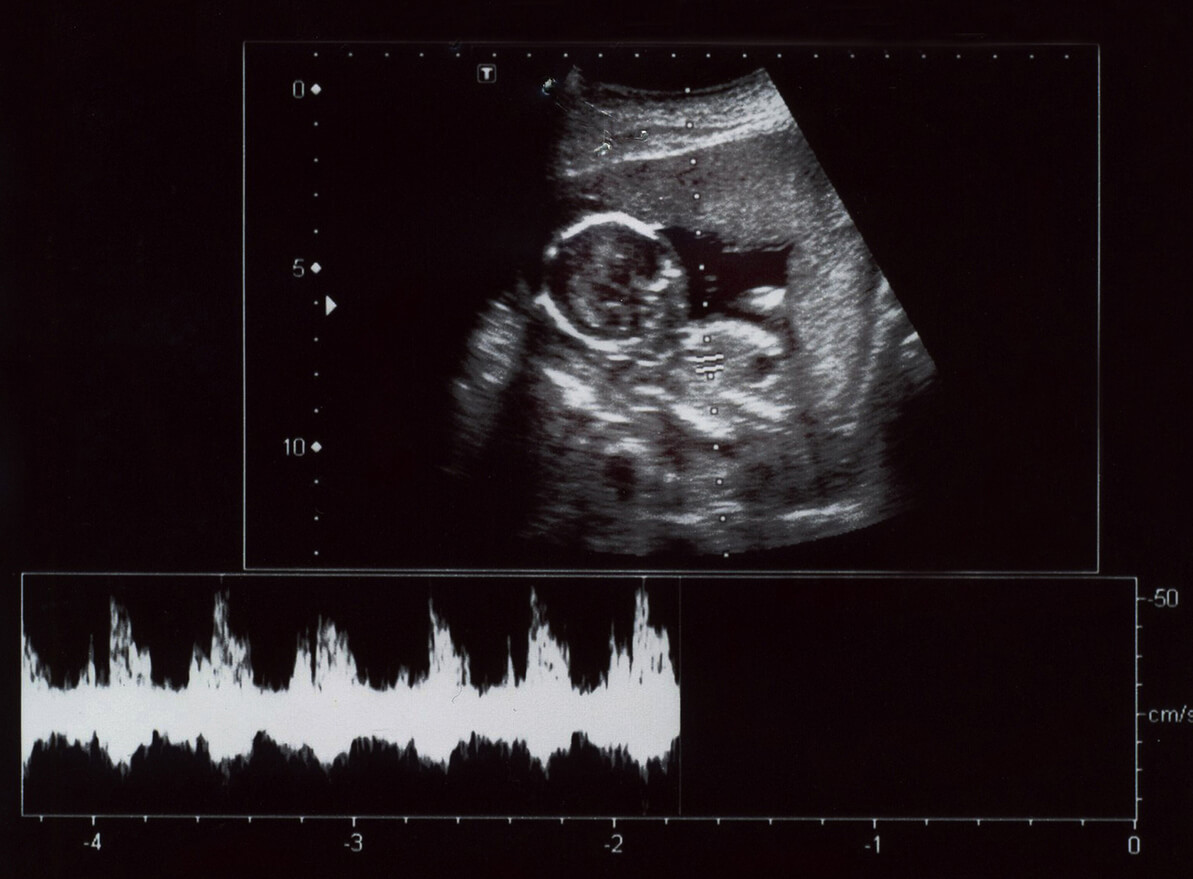

- 2D-ultraääni: Kuvat näkyvät mustavalkoisina. Tätä käytetään eniten.

- Doppler-ultraääni: Väridoppler-ultraäänellä tutkitaan valtimoiden ja laskimoiden verenkiertoa, koska sillä voidaan nähdä nesteen virtaus. Pulsoivalla doppler-ultraäänellä puolestaan tutkitaan verisuonia ja sydäntä.